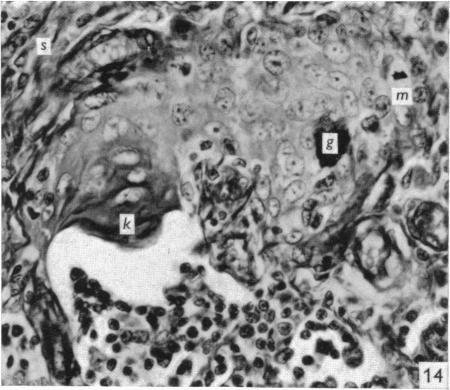

The effect of castration, oestrogens, testosterone and the oestrous cycle on the cortical epithelium of the thymus in male and female rats.

J Anat. 1968 Jun;103(Pt 1):113-33.